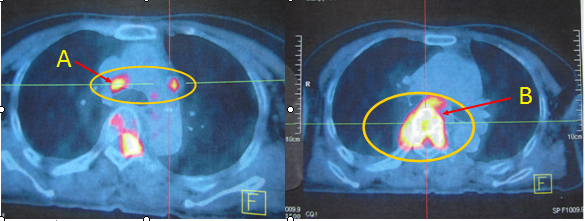

Vì vậy bệnh nhân được chỉ định chụp PET/CT để tìm vị trị tổn thương của ung thư nguyên phát. Kết quả chụp PET/CT không phát hiện thêm vùng tổn thương nào khác và không tìm được ổ ung thư nguyên phát. Cụ thể: chỉ thấy  hình ảnh hạch trung thất tăng hấp thu FDG với SUV max là 5,61, hình ảnh tiêu xương và phá hủy thân đốt sống có chèn ép tủy tại mức D2 -D7tăng hấp thu FDG mạnh với SUV= 11.04, dịch màng phổi phải tăng hấp thu FDG nhẹ.

(Trên hình ảnh PET/CT toàn thân: (A): hạch trung thất; (B): Tổn thương đốt sống có chèn ép tủy sống)